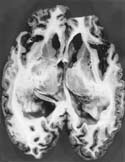

脳波は初期から基礎律動の不規則性がみられ、その後高振幅鋭徐波(PSD)が出現するのがCJDの特徴である。脳CT画像上では初期に軽度の大脳皮質の萎縮、脳室拡大がみられ、その後急速な大脳、小脳の萎縮、著明な脳室拡大、白質のびまん性低吸収域が認められる。CJD解剖例(北大分子細胞病理、長嶋和郎教授供与)の脳割面(写真1)では、大脳、小脳の脳溝拡大と全脳室の拡大が高度であり、大脳、小脳皮質が薄くなる。vCJD例では脳波のPSDはみられず、MRIで視床枕の高電子密度が特異的所見であると報告された。